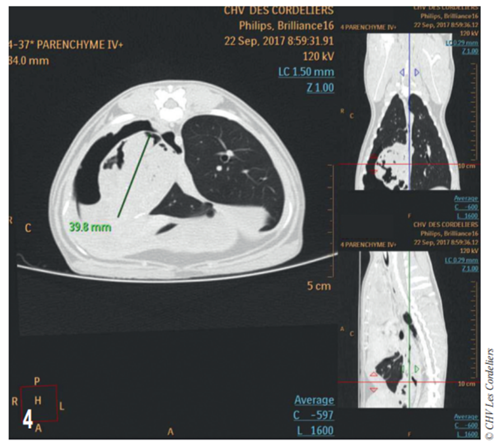

Fig 4

Fig. 4 – Examen tomodensitométrique du 23/09/2017 : mise en évidence d’une masse cavitaire de 39,8 mm de diamètre dans le médiastin crânial droit.

Un examen tomodensitométrique thoracique (Fig. 4) met en évidence un remaniement important du lobe caudal droit avec présence d’un pneumothorax et d’une pleurésie associé à une hypertrophie du ganglion bronchique ; il est constaté la présence d’un tissu anormal contre le péricarde dans l’hémithorax droit et dans le médiastin.